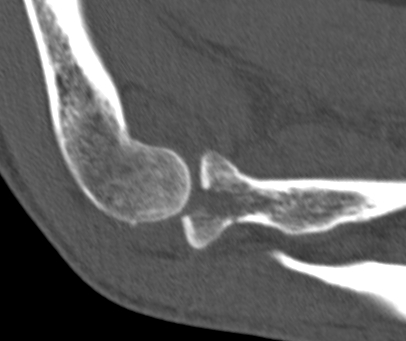

Overstuffing

| Lesser sigmoid notch | Symmetry of ulnohumeral joint |

|---|---|

|

Radial head shoulder articulate with lesser notch

Ensure no gapping of lateral ulnohumeral joint |

- cadaveric study

- increased medial ulno-humeral joint line gapping with overlengthening of 6 or 8 mm

- increased lateral ulno-humeral joint line gapping with overlengthening of 2 mm